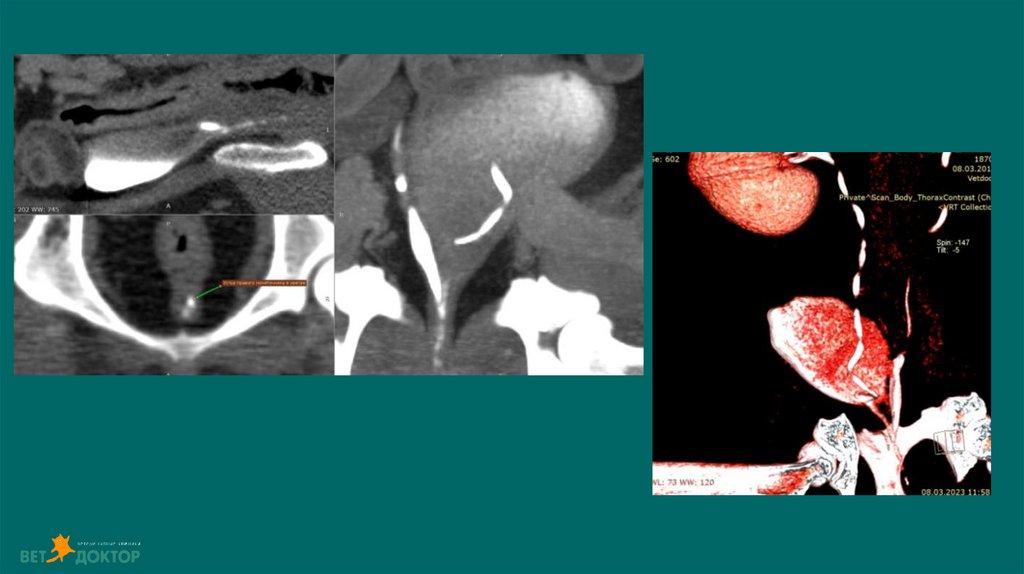

36. Уретеролитиаз-гидронефроз

До 98% уретеролитов у кошек и до 50% у собак состоят из оксалата кальция(Berent, 2011).

Диагноз: УЗИ. Рентген. Пиелография. КТ(урография)

37. Обструкция мочеточника

Обструкция приводит к снижению почечного кровотока на 60-% в первые 24 часа и на 80% за

первые 2 недели.(Berent, 2011).

Если обструкция устранена в течении 4 дней, прогноз на восстановление функции почек

хороший. Через 14 дней СКФ восстановится примерно на 50% от первоначального уровня.

При обструкции более 40 дней возможно восстановление только небольшого числа нефронов

или функции почек может быть полностью утеряна( Kyles,2006).

38. УЗИ

Дилатация лоханки более 13 мм - обструкция

При диаметре лоханки более 8мм-высокая

вероятность обструкции

42. Пиелография

Определения локализации обструкции мочеточников у кошек с азотемией

Снижен риск попадания контраста в почки при нефропатии

Техника

Проводится под УЗИ контролем.

Тонкоигольная аспирация содержимого из лоханки(пиелоцентез)

Спинальной иглой или иглой диаметром 22G вводят под углом 45

Введение йодсодержащего контраста йода(Омнипак,Урографин)

Объем контрастного вещества должен составлять половину объема аспирационной мочи

Dominique Penninck, Marc-Andre d Anjou.2008-2015